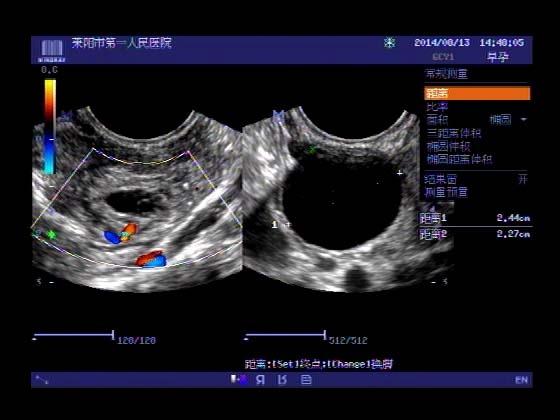

超声入门贴341:宫外孕(阴超的魅力)

女,32岁,停经15天,

一周前在上极医院检查:化验尿HCG阳性,血HCG400多,超声检查问见明显孕囊,让随访。

看见卵黄囊啦~孕囊型的吧?

还能看到卵黄囊,真不错